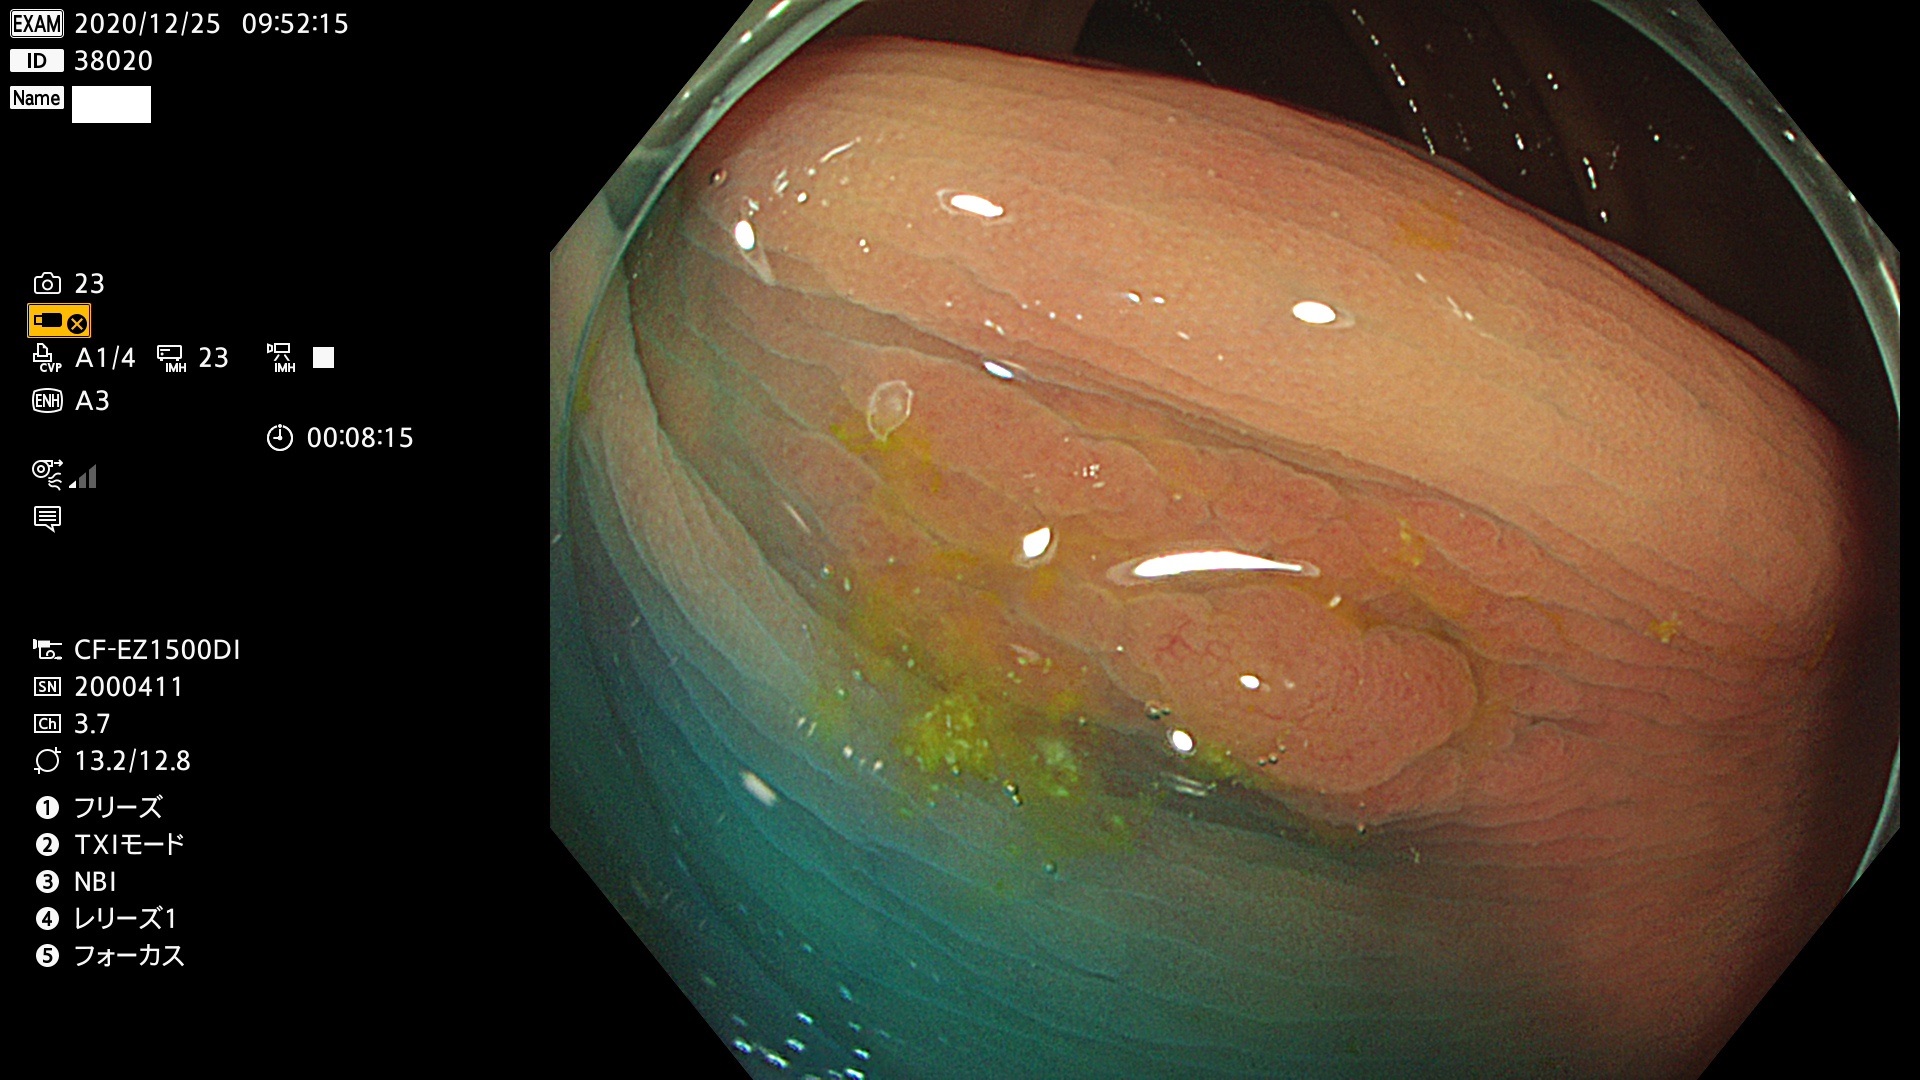

38001 38002 38003 38004 38006(SSAPのみ) 38007 38008 38009 38010 38012 38013 38014 38016 38018 38020 38021 38025 38026 38029 38032 38033 38034 38035 38036 38037(SSAPのみ) 38039 38043 38044 38048 38049 38050 38052 38055 38056 38057 38058 38059 38064(SSAPのみ) 38065 38068 38069 38070 38071 38072 38074 38075 38076 38078 38079 38080 38082 38083 38084 38085(SSAPのみ) 38086 38087 38088 38089 38090 38091 38092 38093 38094 38097 38098 38099

発見困難で危険性の高い平坦型病変(上記100名より抽出)